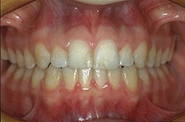

ROLES ESTHETIQUE ET FONCTIONNEL

Toutes les dents sont alignées. L'esthétique et l'efficacité masticatoire sont optimisés.

Avant Après

Avant

Après